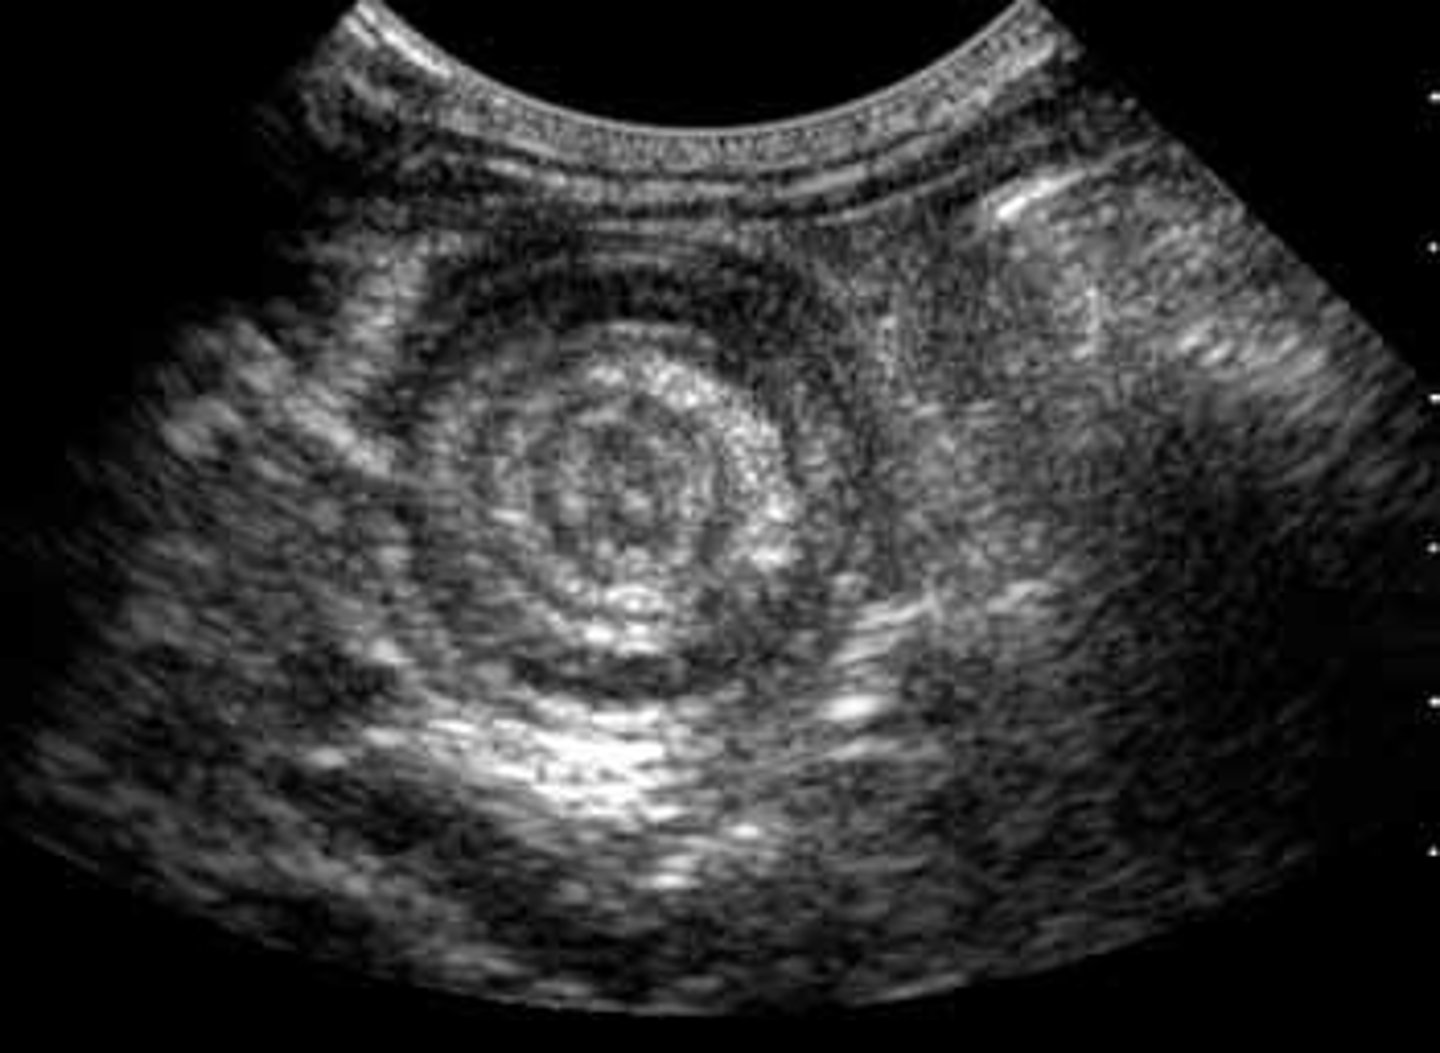

What is the best initial test for intussusception, & what will be seen? What is the best overall test for this condition?

Initial: ultrasound (shows "target sign")

Best: air contrast enema (both diagnostic & therapeutic)